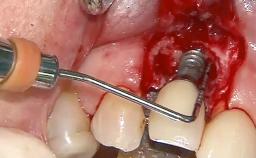

Despite anti-infective surgical treatment, some patients may experience recurrent infection and progressive bone loss requiring additional treatment. This case describes a conservative approach using an implant retrieval tool without the need for excessive bone removal or use of a trephine.

A 65-year-old female patient was referred to the periodontist for assessment and management of infection associated with an implant at site 12. The general dentist had noted suppuration on probing during examination.